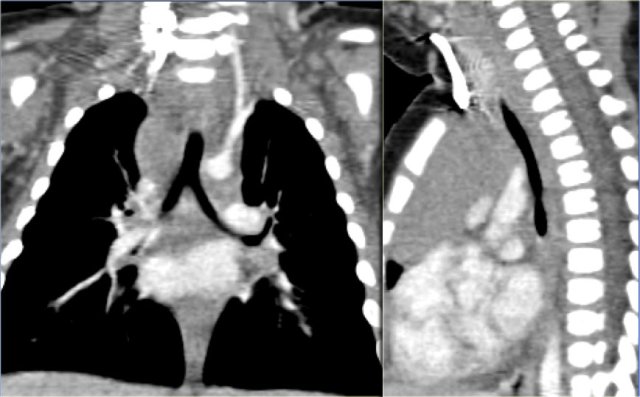

Neuroblastoma presenting as a mass in the posterior mediastinum Neuroblastoma presenting as a mass in the posterior mediastinum

Neuroblastoma

Neuroblastoma typically is fusiform in shape, of soft tissue density; 50% of thoracic tumors have calcifications.

Neuroblastoma Neuroblastoma

Neuroblastoma grows over several interspaces and frequently invades the vertebral canal.

The CT-images show a calcified mass in the posterior mediastinum extending over several vertebrae, which grows into the vertebral canal.